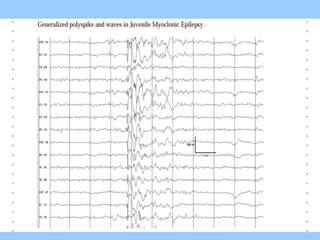

1. The document discusses EEG patterns and findings in various neurological conditions seen in children. It includes descriptions of normal EEG findings as well as abnormal patterns seen in conditions like absence seizures, West syndrome, benign childhood epilepsy with centrotemporal spikes, Lennox-Gastaut syndrome, non-convulsive status epilepticus, subacute sclerosing panencephalitis, and herpes encephalitis.

2. Case studies are presented with clinical histories and EEG findings to illustrate different pathologies. Treatment options are also mentioned for many of the conditions.